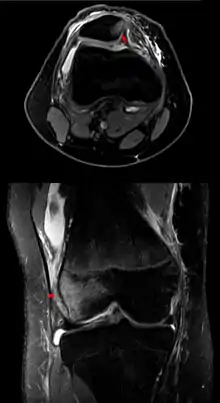

Вивих колінної чашечки

Вивих колінної чашечки (лат. Patella Luxation) — це стан, при якому Patella, або колінна чашечка, дислокується або переміщується зі свого звичайного місця розташування.

Діагноз

Пателла люксаціація визначається мануально ветеринаром при пальпації коліна, щоб побачити, чи ковзає воно всередині суглоба більше, ніж зазвичай очікувалося[2]. Часто власникові собаки можуть сказати, що у його домашнього улюбленця «розпущене коліно», але це не медичний термін, і не правильно використовувати його взаємозамінно з Patella Luxation.

Виявляють чотири ступені Пателла люксаціації:[3]